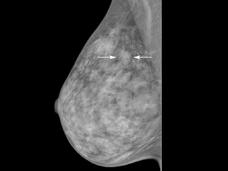

Otro estudio se suma al debate sobre las mamografías en las mujeres mayores

Para las mujeres de 70 o más años, hay un riesgo importante de sobrediagnóstico por el uso de las mamografías de detección de rutina, según un nuevo estudio. Los hallazgos resaltan la necesidad de que las mujeres mayores y los profesionales de la salud conversen sobre los posibles beneficios y daños de continuar con las mamografías de detección.